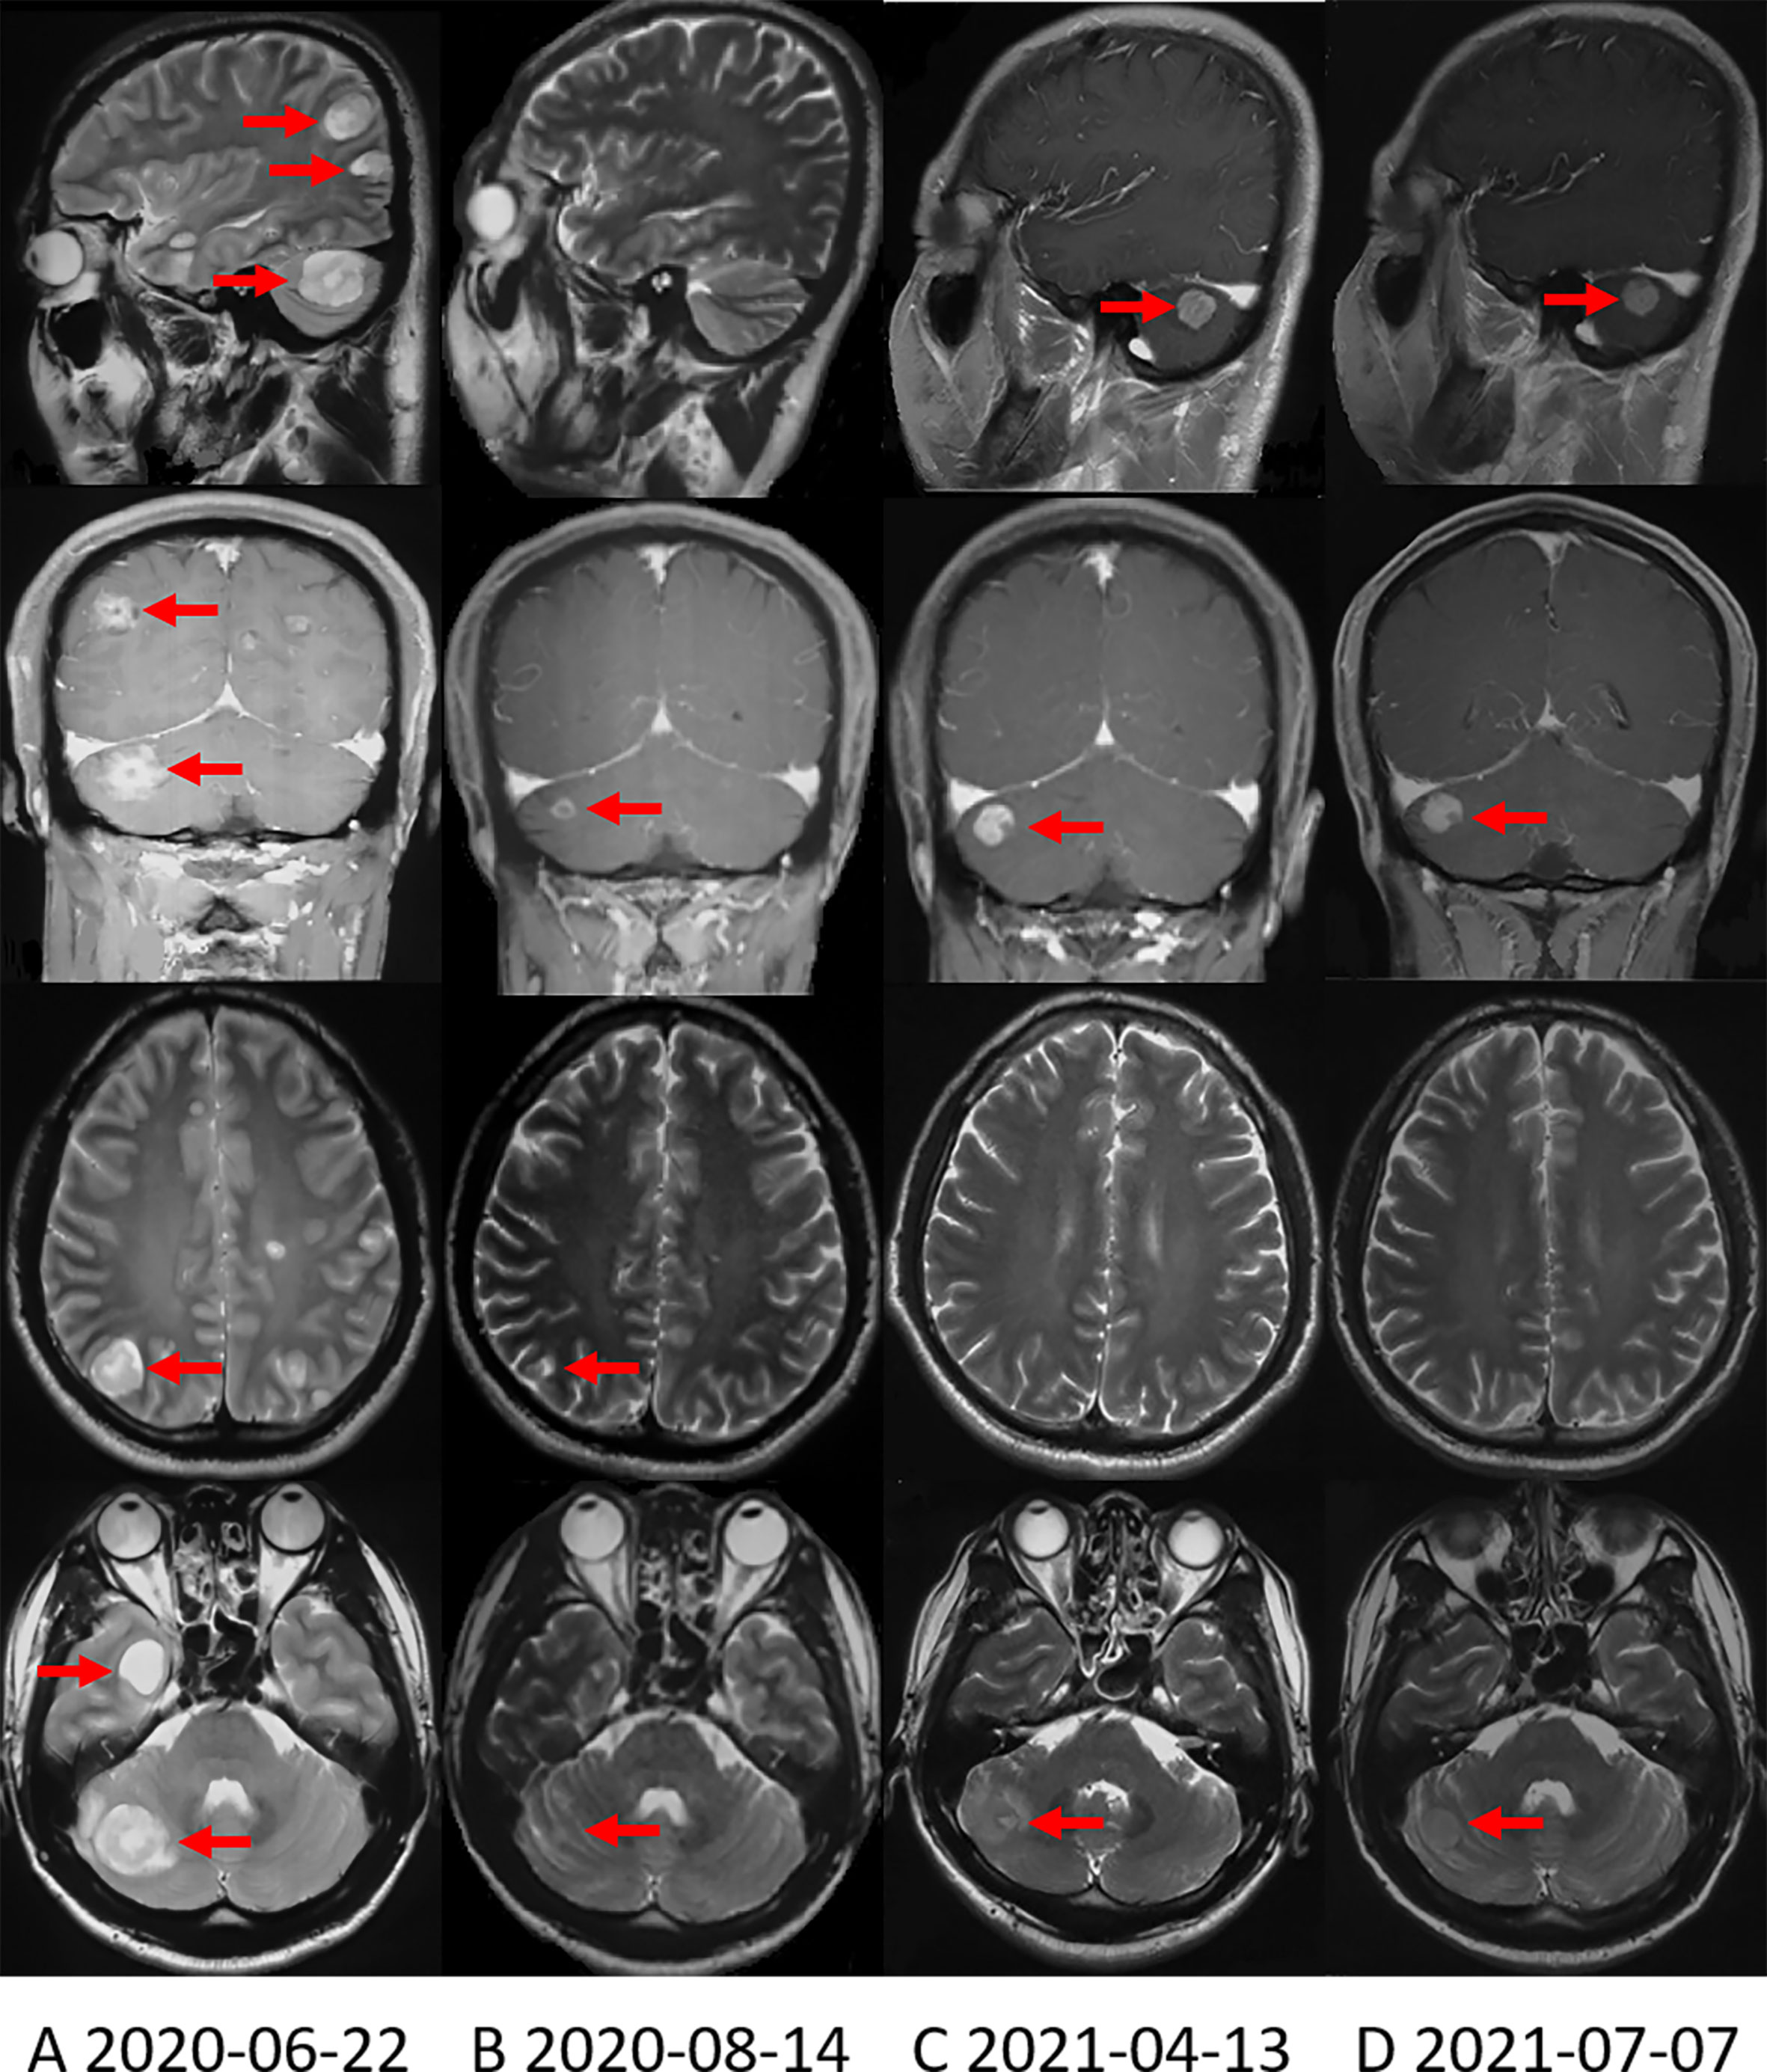

Since October 14, 2019, the patient received 250mg of crizotinib twice daily. Apparent clinical remission was achieved. The palpable left axillary lymph nodes shrank quickly after 3 days of treatment. The patient’s abdominal pain disappeared and CT showed the tumor shrank significantly after 1 month (Figure 1D). The adverse event was grade 1 diarrhea. The treatment lasted for 8 months. On June, 2020, the patient complained of headache, decreased vision in the left eye and disturbance of balance in the left limb, CT and MRI on June 22, 2020 showed a progression in brain metastasis (Figure 2A). Interestingly, the extracranial lesions (Figure 1E) and serum CA19-9 remained durable responses. Then, Alectinib 600mg twice a day was administered from 23 June, 2020. The above symptoms relieved rapidly and no adverse events occurred during the treatment. The brain lesions shrank significantly (MRI scan on August 14, 2020, Figure 2B). However, after continuing the treatment for nearly 10 months, on April 13, 2021, the patient’s reexamination of the brain MRI showed that the right cerebellum (Figure 2C) and left frontal lobe lesions increased in size. The brain metastases were progressing, but the extracranial lesions were still stable (Figure 1F). The patient underwent a circulating tumor DNA (ctDNA) test on April 26, 2021. As a result, 10 gene mutations were found: AMER1 p.S794*, ATR p.E2626*, CCND2 p.A109D, CHEK1 p.S193Y, CREBBP p.S1599R, ERCC4 p.T660K, IL7R p.H279N, MRE11A p.A147D, SETD2 p.R87M, SETD2 p.M1080_E1081delinsI*, ctDNA testing has not yet prompted the basis for medication. Therefore, on the basis of continuing the application of alectinib, the patient received brain radiotherapy from June 1 to July 3, 2021. In the latest examination, brain lesions (Figure 2D) and other parts (Figure 1G) of the disease are stable, and the patient is currently being treated with alectinib.

Figure 2 Brain MRI shows the change in brain metastases with treatment. (A) Brain MRI when the brain metastases first appeared. (B) Brain MRI showed that the brain metastases were significantly reduced after applying alectinib for nearly 2 months. (C) On April 13, 2021, Brain MRI showed that the right cerebellum lesion increased in size. (D) On July 7, 2021, the most recent Brain MRI showed that the brain metastases were stable.